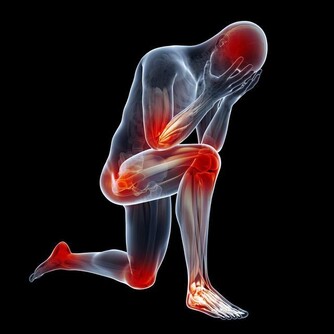

現代人因為長時間久坐、用電腦和壓力等因素,造成不少人都有肩頸酸痛、緊繃的困擾,

這是因為我們脖子周圍的肌肉一直維持在前側緊縮,後側則往前伸的狀態,

這樣長時間的緊繃會對肌肉造成負擔,造成血液循環不良!

這時候我們就需要適時的來伸展一下肩頸附近的肌肉,抒緩酸痛等不適感。這次要來和大家介紹的伸展操非常簡單,每天都只要花 1 分鐘的時間就能有效的改善肩頸酸痛、緊繃等困擾!